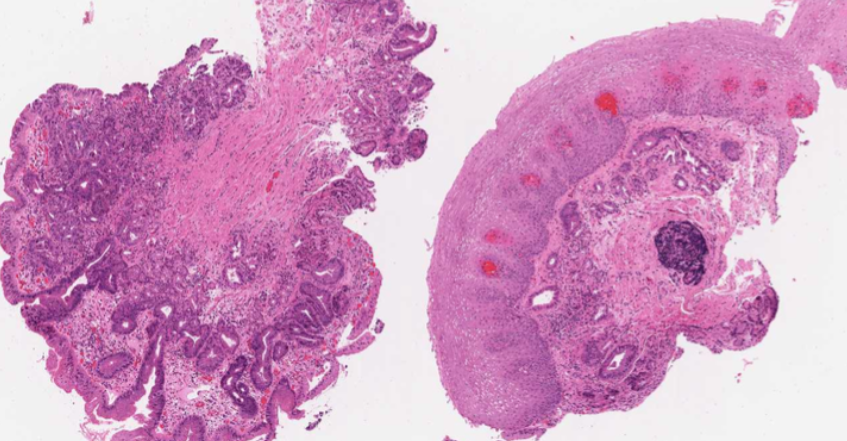

CRC

65yo male presents with a 6 month history of rectal bleeding and change in bowel habit. Associated with this he has a many month history of unintentional weight loss and fatigue